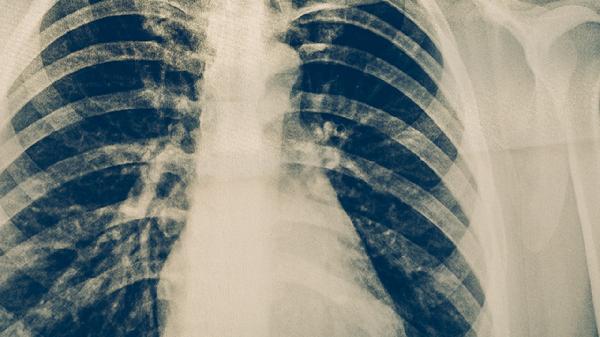

肺癌患者除规范治疗外,需保证优质蛋白摄入如鱼肉、蛋类,适量补充维生素C和硒元素。避免吸烟及接触油烟等致癌物,进行呼吸功能锻炼如腹式呼吸。定期复查胸部CT和肿瘤标志物,出现咯血、骨痛等症状需立即就医。